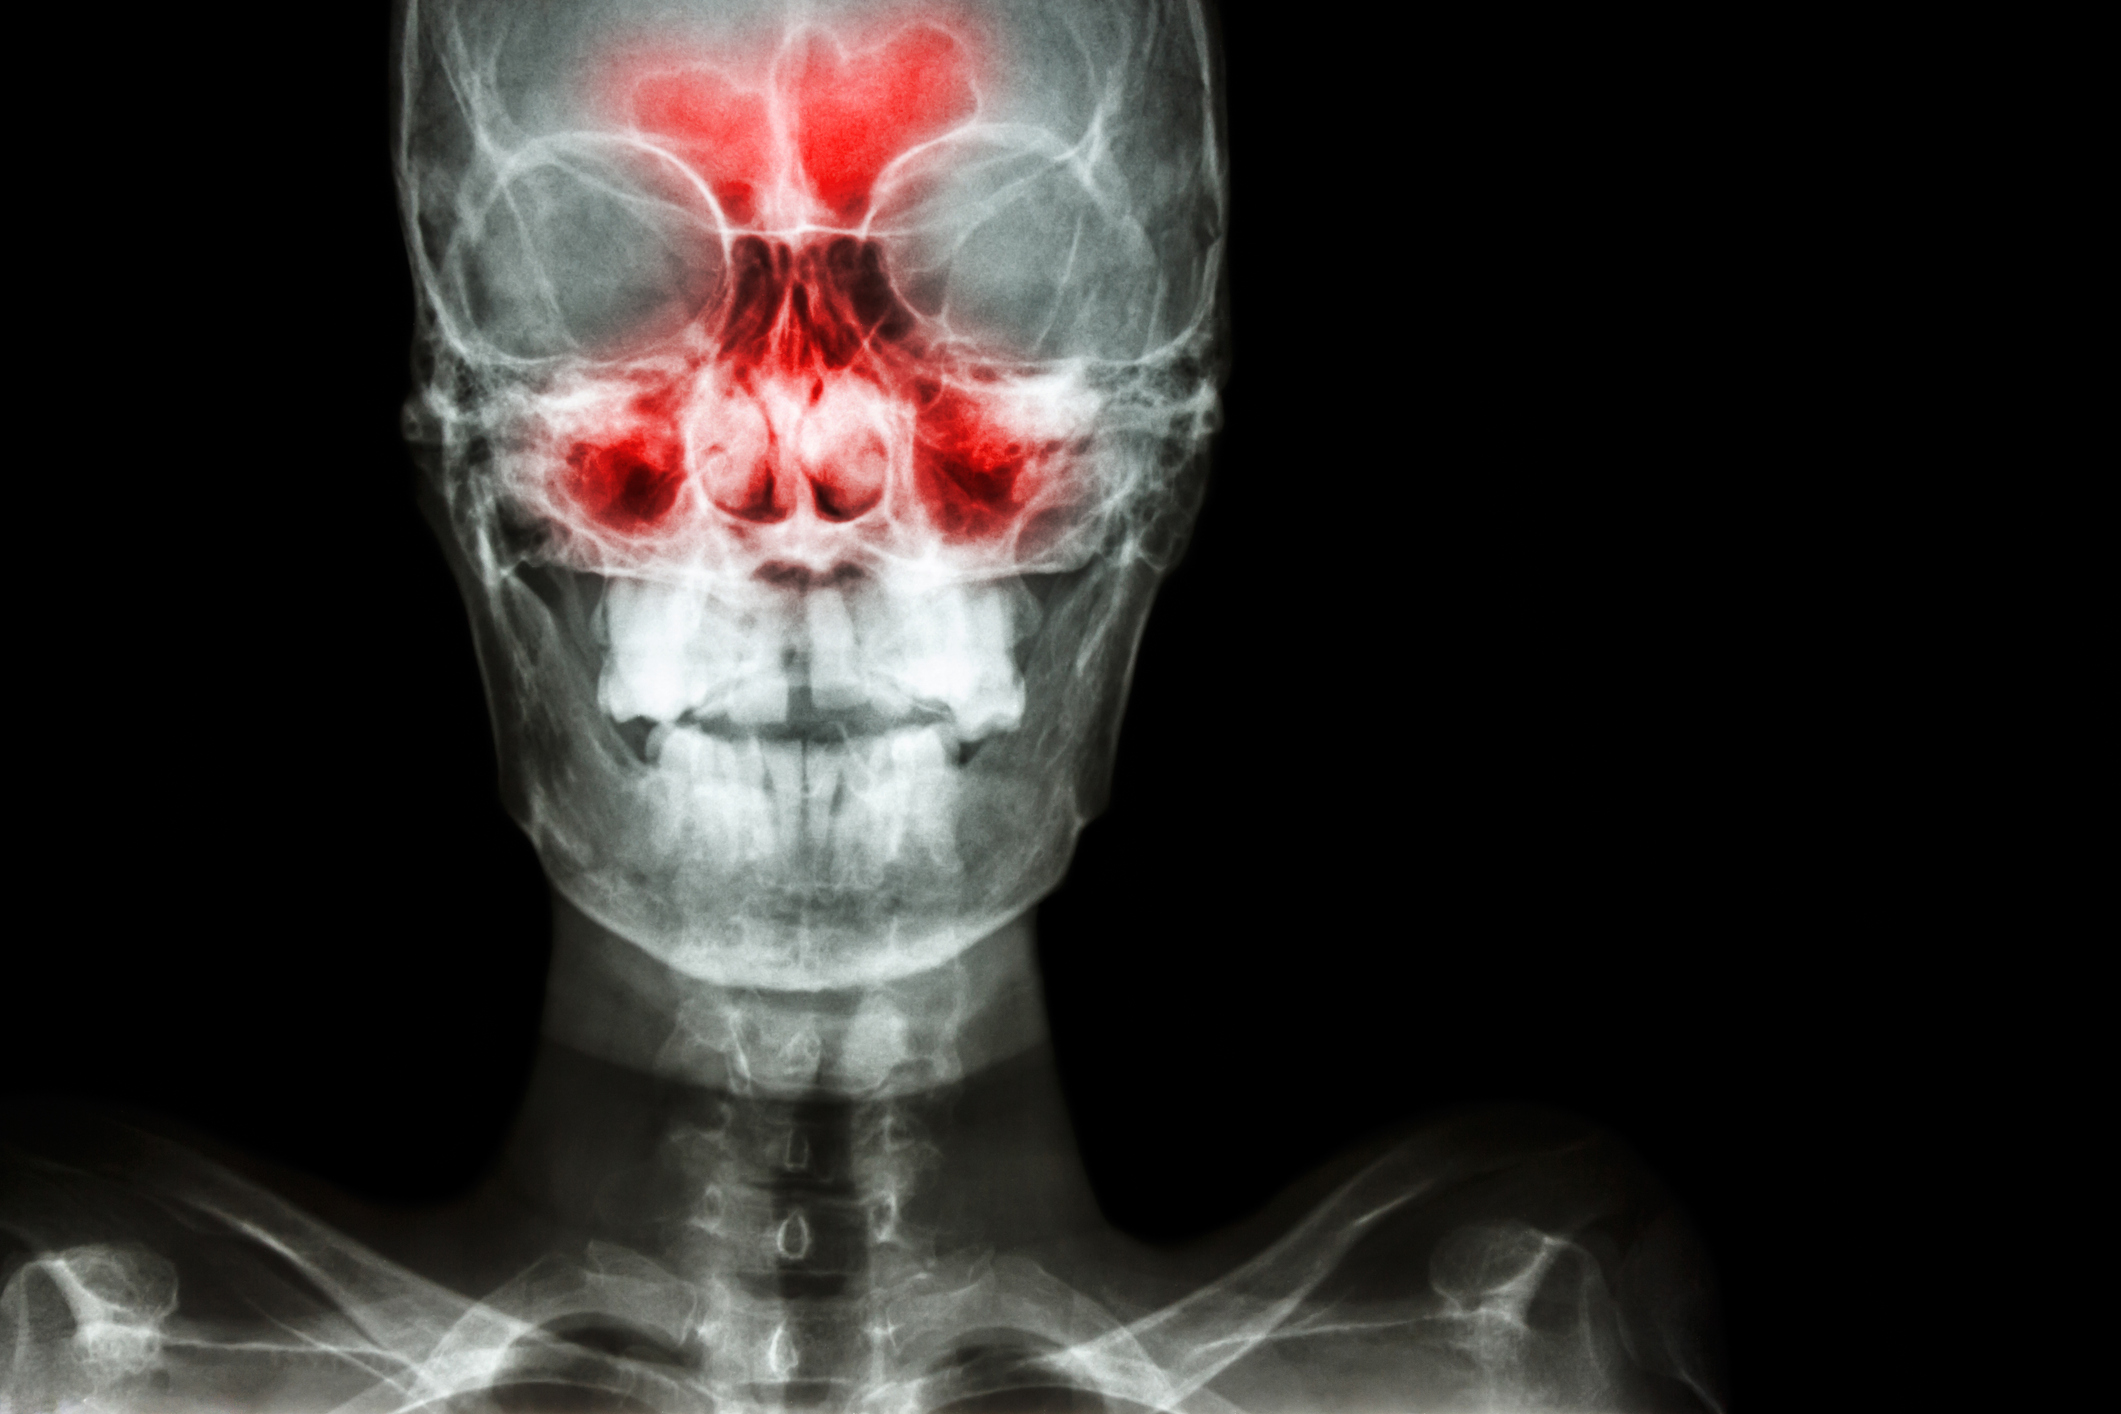

Endoscopic sinus surgery is usually performed as an outpatient procedure with the patient under general anesthesia (asleep). During the surgery: The sinus surgeon inserts an endoscope — a thin camera rod with a light at the end — into one nostril and uses it to magnify and visualize the sinus tissues.